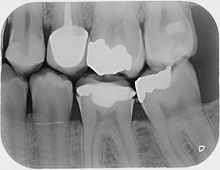

Dental X-rays (radiographs) are images of your teeth that your dentist uses to evaluate your oral health. These X-rays are used with low levels of radiation to capture images of the interior of your teeth and gums. This can help your dentist to identify problems, like cavities, tooth decay, and impacted teeth. Dental X-rays are a useful diagnostic tool when helping your dentist detect damage and disease not visible during a regular dental exam. The frequency of getting X-rays of your teeth often depends on your medical and dental history and current condition. Some people may need X-rays as often as every six months; others with no recent dental or gum disease and who visit their dentist regularly may get X-rays only every couple of years.

Dental radiographs are commonly called X-rays. Dentists use radiographs for many reasons: to find hidden dental structures, malignant or benign masses, bone loss, and cavities. A radiographic image is formed by a controlled burst of X-ray radiation which penetrates oral structures at different levels, depending on varying anatomical densities, before striking the film or sensor. Teeth appear lighter because less radiation penetrates them to reach the film. Dental caries, infections and other changes in the bone density, and the periodontal ligament appear darker because X-rays readily penetrate these less dense structures. Dental restorations (fillings, crowns) may appear lighter or darker, depending on the density of the material.